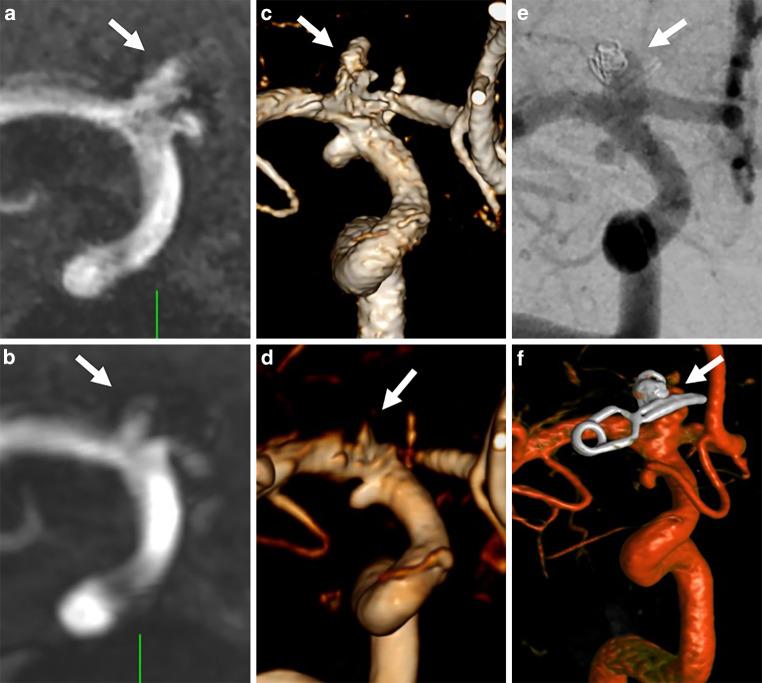

On 3D-DSA, 25 aneurysms in 17 patients were detected. On conventional TOF, 23 aneurysms were detected (sensitivity: 92.6%). On UHR-TOF, 25 aneurysms were detected (sensitivity: 100%). Image quality was not significantly different between TOF and UHR-TOF (p = 0.17). Aneurysm dimension measurements were significantly different between conventional TOF (3.89 mm) and 3D-DSA (4.2 mm, p = 0.08) but not between UHR-TOF (4.12 mm) and 3D-DSA (p = 0.19). Irregularities and small vessels at the aneurysm neck were more frequently correctly depicted on UHR-TOF compared to conventional TOF. Comparison of the planned framing coil diameter and flow-diverter (FD) diameter revealed neither a statistically significant difference between TOF and 3D-DSA (coil p = 0.19, FD p = 0.45) nor between UHR-TOF and 3D-DSA (coil: p = 0.53, FD 0.33). The CNR was significantly higher in conventional TOF (p = 0.009).

In this pilot study, ultra-high-resolution TOF-MRA visualized all aneurysms and accurately depicted aneurysm irregularities and vessels at the base of the aneurysm comparably to DSA, outperforming conventional TOF. UHR-TOF with compressed sensing reconstruction seems to represent a non-invasive alternative to pre-interventional DSA for intracranial aneurysms.

在 3D-DSA 上,17 例患者中的 25 个动脉瘤被检测到。在常规 TOF 上,检测到 23 个动脉瘤(灵敏度:92.6%)。在 UHR-TOF 上,检测到 25 个动脉瘤(灵敏度:100%)。TOF 与 UHR-TOF 之间的图像质量无显著差异(p=0.17)。常规 TOF 测量的动脉瘤直径(3.89mm)与 3D-DSA 测量的直径(4.2mm,p=0.08)存在显著差异,但 UHR-TOF 测量的直径(4.12mm)与 3D-DSA 测量的直径无显著差异(p=0.19)。UHR-TOF 较常规 TOF 更能准确显示瘤颈处的不规则及小血管。计划使用的框架线圈直径和血流导向装置(FD)直径与 3D-DSA 相比,TOF 与 3D-DSA 之间无显著差异(线圈:p=0.19,FD:p=0.45),UHR-TOF 与 3D-DSA 之间亦无显著差异(线圈:p=0.53,FD:p=0.33)。常规 TOF 的 CNR 显著更高(p=0.009)。

在本研究中,UHR-TOF 可可视化所有动脉瘤,并与 DSA 相比准确显示动脉瘤不规则及瘤颈处血管,其表现优于常规 TOF。应用压缩感知重建的 UHR-TOF 似乎代表了一种替代术前介入性 DSA 用于颅内动脉瘤的非侵入性方法。